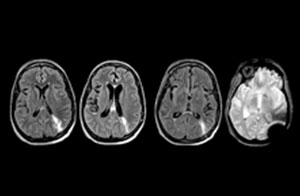

When neurological emergencies require diagnostic imaging, common practice in the ED has been to perform CT rather than MRI, even when MRI could potentially produce more informative diagnostic images of spinal cord damage, disc protrusions, soft tissue injuries, and stroke pre-cursors. [1,2] The main reason is that timing is essential in emergency cases, and CT is generally faster than MRI. The St. Joseph’s Hospital and Medical Center is now challenging this paradigm by offering rapid MRI scans within its Neurologic ED and seeing that it helps them make a richer diagnosis.

efficient as CT for referring physicians, then physicians would probably prefer MRI over CT in part of the cases. Reducing the number of CT scans for patients less than 40 years of age without significant acute findings, such as acute stroke, was also a main reason for introducing MRI into the ED. “MRI is a better test for identifying soft tissue abnormalities in the brain. What really influenced the decision on the administrative side, was the total radiation dose received by ED patients, and how this could be reduced by introducing MRI in the ED”.

“In the past, CT scans were performed because of their availability and rapid turnaround time” Dr. Karis argues, “but if an MRI could be as efficient as CT for referring physicians, then physicians would probably prefer MRI over CT in part of the cases. Reducing the number of CT scans for patients less than 40 years of age without significant acute findings, such as acute stroke, was also a main reason for introducing MRI into the ED. “MRI is a better test for identifying soft tissue abnormalities in the brain. What really influenced the decision on the administrative side, was the total radiation dose received by ED patients, and how this could be reduced by introducing MRI in the ED”.